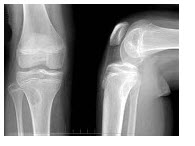

A.瘤体内出现透亮区

B.软骨帽增厚,发生于长骨者超过1cm